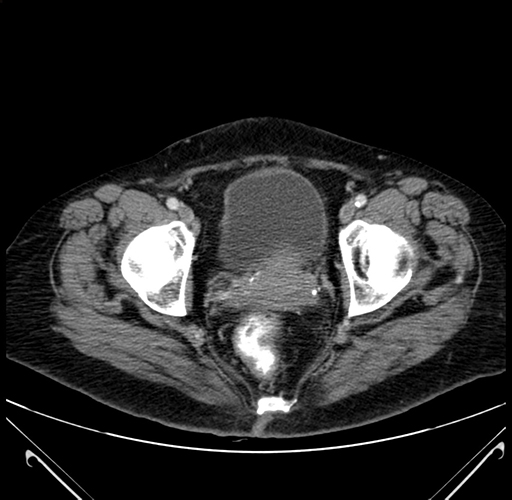

Axial Venous